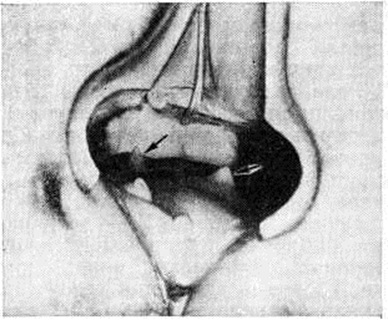

ПроктитПроктит (proctitis; греческий proktos задний проход, прямая кишка + -itis) — воспалительный процесс, поражающий преимущественно слизистую оболочку прямой кишки. Проктит протекает остро, подостро и хронически (смотри полный свод знаний: Воспаление). При остром течении выделяют катаральную, гнойную, язвенную, язвенно-некротическую формы (цветной рисунок 1—4), а также фибринозную и геморрагическую. Возбудитель инфекции может проникать в прямую кишку различными путями: через рот (дизентерия, холера и другие), гематогенно, через задний проход (гонорея, мягкий шанкр, паховый лимфогранулематоз), при огнестрельных или других ранениях, с инородными телами. При таких заболеваниях прямой кишки и соседних органов, как геморрой, парапроктит, полипы и рак прямой кишки, абсцесс дугласова пространства, простатит, цистит, вагинит может наблюдаться вторичный проктит. Проктит может являться проявлением инфекционные поражения всей толстой кишки (при дизентерии, холере и другие); отравления ядами, грибами; микотического поражения при длительном лечении антибиотиками либо проявлением воспаления ограниченных отделов кишки, например, при хронический колитах, сопровождающихся запорами (застойный проктит). Возможен также проктосигмоидит, сфинктерный Проктит (анит), например, при трещине заднего прохода, папиллит, наблюдающийся при воспалении анальных сосочков (рисунок), криптит, при воспалении морганиевых крипт (смотри полный свод знаний: Задний проход). Длительно текущий, трудно поддающийся лечению лучевой Проктит нередко наблюдается после лучевой терапии злокачественных опухолей органов таза (смотри полный свод знаний: Лучевые повреждения). Острый Проктит проявляется постоянными болями в прямой кишке, непроизвольным истечением из неё серозных, гнойных, слизистых, геморрагических выделений, повышением температуры тела. Функция кишки нарушена: наружный сфинктер заднего прохода ослаблен, нередко задний проход зияет. Постепенно под влиянием лечения симптомы острого Проктит стихают, может наступить выздоровление или Проктит переходит в подострую либо хронический стадию. Примесь слизи в каловых массах или обнаружение её при ректороманоскопии свидетельствует о незаконченном воспалительном процессе. В исходе острого проктита, особенно гонорейного, а также язвенного, возможны рубцовые сужения прямой кишки. Диагноз Проктит базируется на данных осмотра области заднего прохода, ректального исследования (смотри полный свод знаний), ректороманоскопии (смотри полный свод знаний). При исследовании обнаруживается гиперемия, отёчность слизистой оболочки кишки. Характерны наложения слизи, фибрина, кровоизлияния, кровоточивость, изъязвления. Важную роль в диагностике воспалительных заболеваний прямой и сигмовидной кишок имеет цитологический исследование кишечного содержимого. Лечение острого и подострого Проктит следует начинать с устранения вызвавших его причин. Рекомендуют постельный режим, ограничение употребления пищевых продуктов, содержащих много клетчатки, исключают жареные, острые блюда, запрещают приём спиртных напитков. Пища должна быть механически щадящей. Назначают антибиотики, сульфаниламиды, тёплые клизмы 2—3 раза в день с раствором перманганата калия, риванола, 2% раствором колларгола или протаргола, с настоем ромашки или с рыбьим жиром. Хорошие результаты даёт введение в прямую кишку пенообразных антисептиков. Полезны сидячие ванны и промежностные тёплые души с антисептическими растворами. Прогноз чаще благоприятный. Однако в ряде случаев при несвоевременно начатом лечении возможен переход в хронический форму. Хронический Проктит имеет три основные формы — гипертрофическую, нормотрофическую и атрофическую. При гипертрофической форме эндоскопически отмечаются утолщённые, отёчные, иногда избыточно разросшиеся рыхлые складки слизистой оболочки с несколько увеличенными легко различимыми лимфатических, фолликулами (цветной рисунок 5). При нормотрофической форме складки слизистой оболочки имеют нормальный вид. При атрофической форме (цветной рисунок 6) слизистая оболочка прямой кишки истончена, сухая со сглаженными складками и просвечивающими сосудами, легко ранима. При всех формах хронического Проктит нередко субъективные ощущения отсутствуют, в каловых массах обнаруживается небольшая примесь слизи. При бессимптомном хронический Проктит больные редко обращаются к врачу. |

При подострых или хронических локальных воспалительных процессах в прямой кишке (криптит, папиллит), сопровождающихся выраженными болевыми ощущениями, успех приносит оперативное лечение — удаление поражённой крипты или воспалённых анальных сосочков.